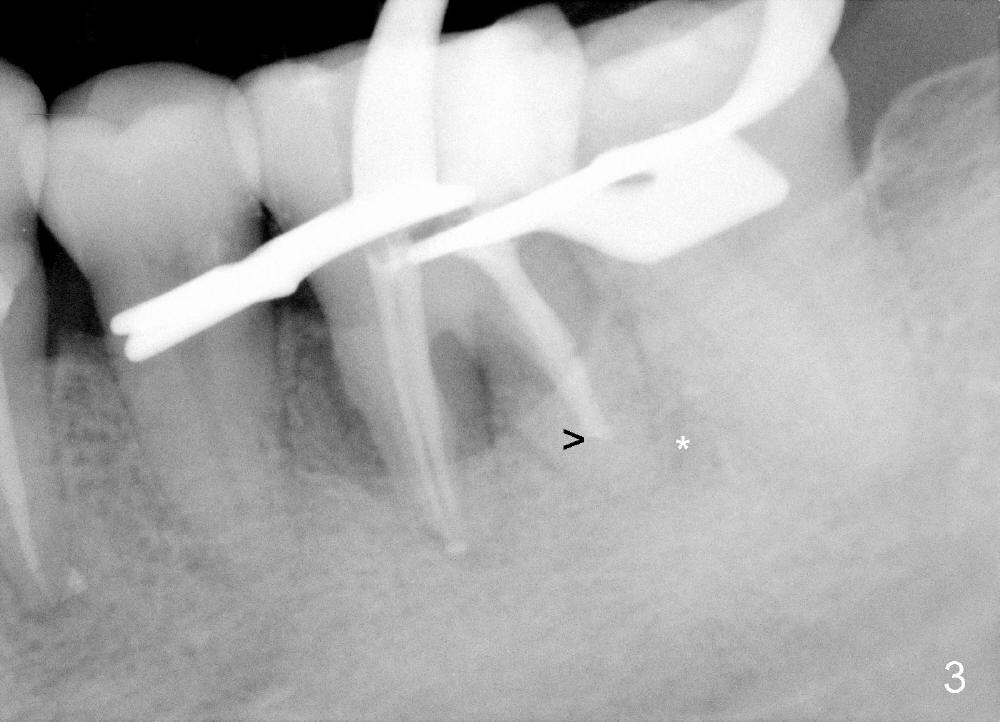

Considering severe bone resorption, a 6.9x10 mm bone-level (Fig.4) or 7x14 mm gingiva-level (Fig.5) implant does not seem to be long enough to achieve primary stability. Probably a 7x17 mm gingiva-level implant is more appropriate, but it carries more risk of nerve injury. Be careful. Take several intraop PAs for depth confirmation. Try shorter osteotomy and implant first and use longer one if necessary.

Use Lindamann bur to make a slot on the septum before osteotomy. The slot should be slightly more lingual to prevent buccal thread showing through. The implant to be placed should be large enough to obtain primary stability, but not too large. Too large an implant tends to make the buccal bone thin or perforated.

Immediate provisional is highly necessary, due to a previous history of shifting of a neighboring tooth. Anyway, is the buccal plate defective?